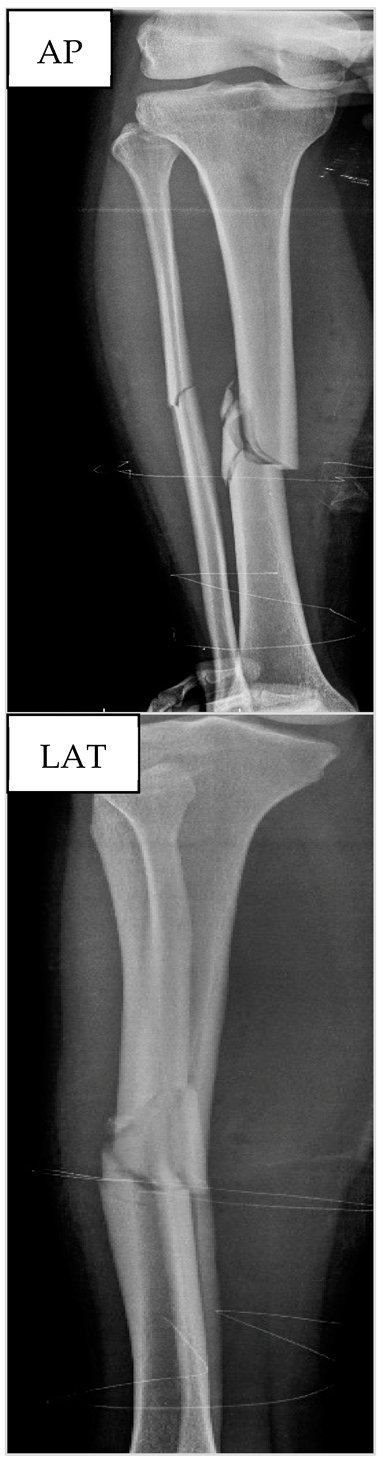

3.3. Patient nº3